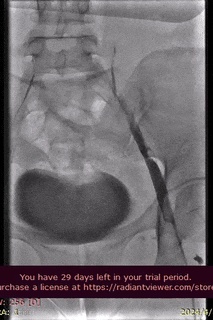

手术过程